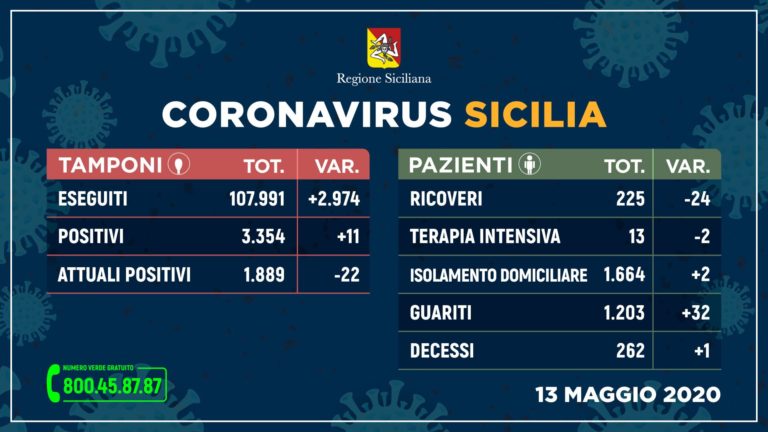

In Sicilia 11 nuovi positivi al Covid e un decesso, aumentano i guariti

PALERMO (ITALPRESS) – Dall’inizio dei controlli in Sicilia, i tamponi effettuati sono stati 107.991 (+2.974 rispetto a ieri), su 96.860 persone: di queste sono risultate positive 3.354 (+11), mentre attualmente sono ancora contagiate 1.889 (-22), 1.203 sono guarite (+32) e 262 decedute (+1). E’ quanto emerge dal quadro riepilogativo della situazione nell’Isola, in merito all’emergenza Coronavirus, cosi’ come comunicato dalla Regione Siciliana all’Unita’ di crisi nazionale.

Degli attuali 1.889 positivi, 225 pazienti (-24) sono ricoverati – di cui 13 in terapia intensiva (-2) – mentre 1.664 (+2) sono in isolamento domiciliare.